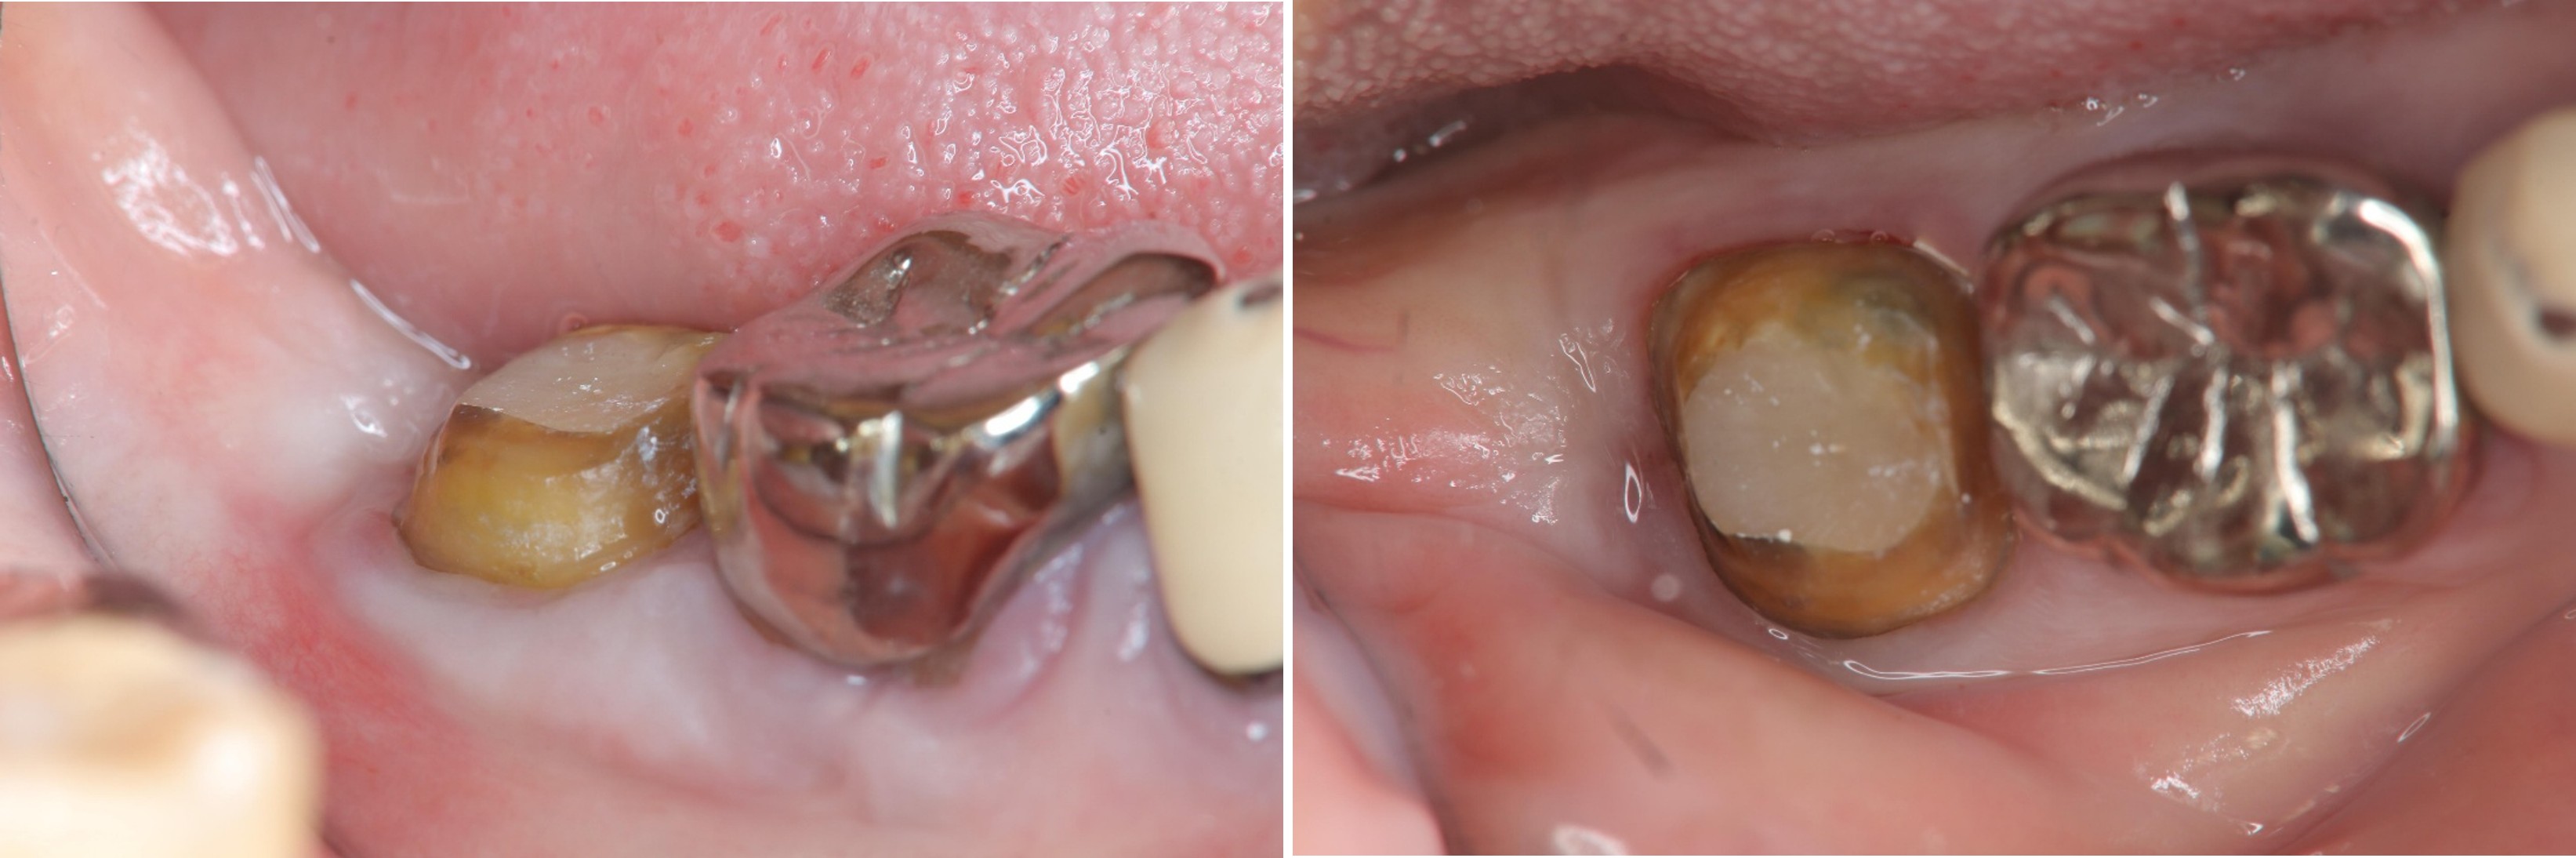

6週牙齦癒合良好

取面弓,上咬合器

製作固定假牙

因受力考量,製作金屬燒付瓷牙

術前、術後比較